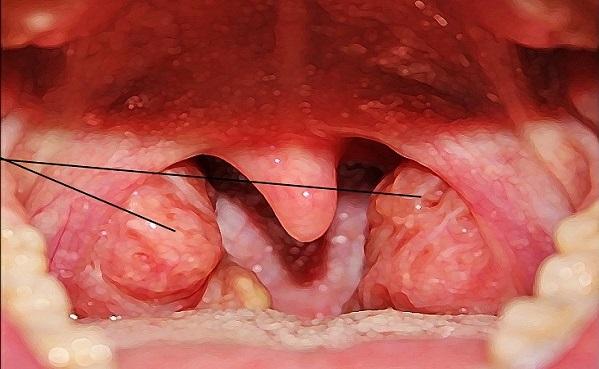

Из-за сниженного иммунитета и частых простудных заболеваний аденоиды могут увеличиваться в размерах. Это приводит к отеку миндалин, что затрудняет нормальное дыхание.

Симптомы возникновения аденоидов вызывают дискомфорт. Ребенок начинает дышать через рот, особенно это заметно ночью. Потеря аппетита, общая вялость, раздражительность — все это может быть признаками наличия аденоидов. Голос становится низким и хриплым, также возникают жалобы на головные боли. Накопившаяся слизь в носоглотке вызывает кашель из-за раздражения слизистой оболочки.

Лечение может быть как консервативным, так и оперативным. Консервативная терапия включает прием противокашлевых средств (например, Синекод) или отхаркивающих препаратов (например, Лазолван, Бромгексин), антигистаминных средств (например, Зиртек, Зодак), а также использование сосудосуживающих капель для носа. Полезно проводить регулярные промывания носа солевыми растворами, такими как Аквамарис или обычный физраствор.